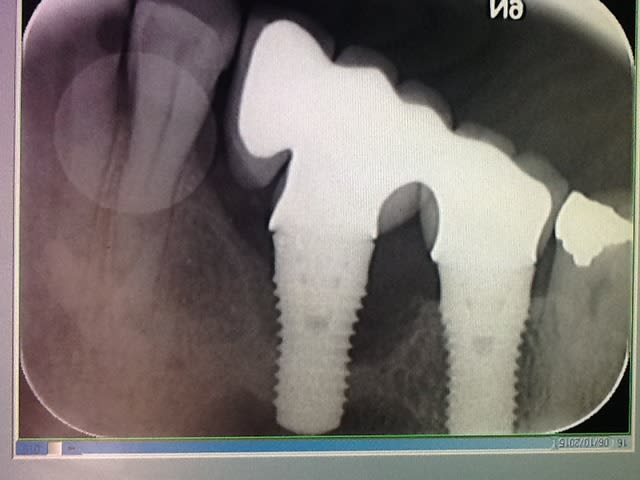

la péri-implantite touche un implant en 16 ( un straumann TE) posé il y a plus de 10 ans par un confrère spécialisé en chir paro-implanto....maintenant décédé.

le patient présente un saignement au sondage et une suppuration, ainsi qu'une douleur uniquement à la palpation vestibulaire en regard de l'implant.

impossible de savoir si l'implant est mobile sans déposer( fraiser) le bridge scellé...

on peut voir un léger hiatus avec la prothèse, mais je n e pense pas (?) que cela soit en cause.

Il reste 3 spires (peut-être) ostéo-intégrées. C'est fini pour lui.

péri-implantite de plus du tiers des spires, pronostic faible

attention au sinus

Cause de la péri-implantite? probablement mauvais ajustement pilier implant, les bactéries aiment les espaces vides...

amha, çà va être difficile de sauver cet implant car la destruction osseuse est quand même sacrément importante et que c'est un implant tissue level et non un bone level...donc tenter une ROG en le laissant en place est vouée à l'échec d'avance car tu ne pourras pas refermer de manière étanche et sans tension les tissus au dessus...comme çà peut se faire avec un tissue level...

il y a peut être à redire sur la prothèse...mais on est sur un implant tissue level les gars!!! donc quand même à distance raisonnable de l'os!